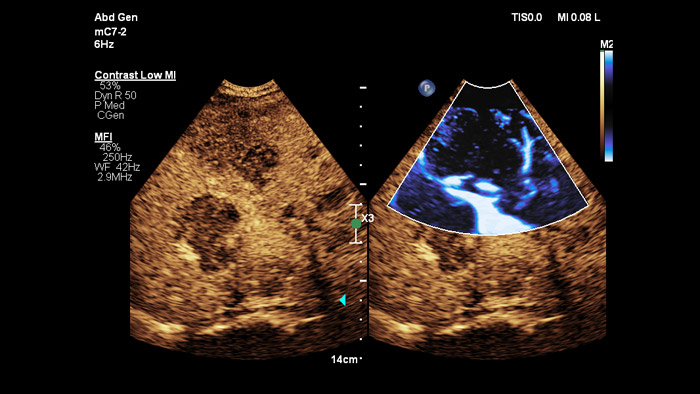

超音波造影剤は肝臓診断における超音波診断装置の役割を変え、ユーザーはリアルタイムで肝臓病変の増強パターンを観察して、迅速で確実な診断を行えます。フィリップスの超音波診断装置を使用することで、造影超音波検査は標準ワークフローへとシームレスに統合し、動脈、門脈、後期相のスキャンで高精細な描出を可能にします。